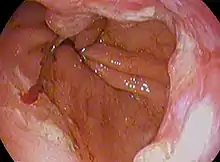

Endoscopic image of Barrett esophagus – a frequent precursor of esophageal adenocarcinoma

Endoscopic image of Barrett esophagus – a frequent precursor of esophageal adenocarcinoma Endoscopy and radial endoscopic ultrasound images of a submucosal tumor in the central portion of the esophagus